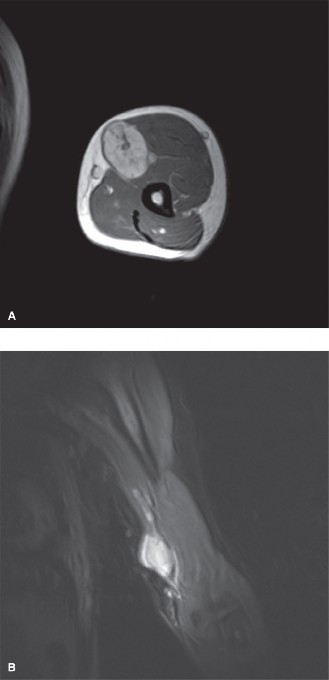

A 38-year-old female is referred to your office by her primary physician for a mass on her neck. It is painle…